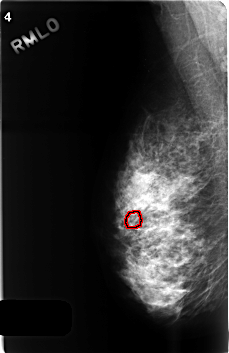

FILE: C_0499_1.RIGHT_MLO.OVERLAY

TOTAL_ABNORMALITIES 1

ABNORMALITY 1

LESION_TYPE CALCIFICATION TYPE PLEOMORPHIC DISTRIBUTION CLUSTERED

ASSESSMENT 4

SUBTLETY 3

PATHOLOGY BENIGN

TOTAL_OUTLINES 1

BOUNDARY